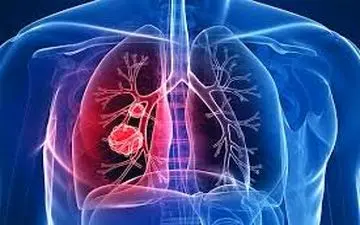

با همه گیری کووید ۱۹ در جهان، تشخیص ابتلا به سرطان ریه و یا ویروس کرونا به یک چالش برای کادر درمانی تبدیل شده است.

فوق تخصص ریه گفت: بیماری که دچار سرفه، بدن درد، ضعف، تب، اختلال بویایی و چشایی شده است، به احتمال زیاد به کرونا مبتلا…